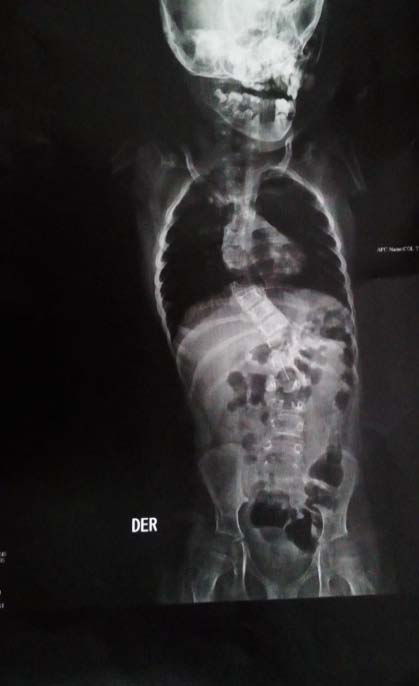

The Bohring-Opitz Syndrome (BOS, OMIM 605039) is caused by de novo or nonsense mutations in the ASXL1 gene (OMIM 612990) (3), that accounts for about 50% of the cases that meet the clinical criteria. The gene locus is located on chromosome 20q11.21, contains 13 exons and codes for the sex-combs-like 1 protein, which is a polypeptide of 1543 amino acids (2,4). The sex-combs-like 1 protein is involved in the remodeling of chromatin in localized areas and helps to activate and silence the transcription of different genes involved in the regulation of the expression of HOX genes, involved in embryonic development for determination of the basic structure and orientation of the embryo (5), which proposes a mechanism of loss of function, that is, haploinsufficiency, as the fundamental cause of the BOPS clinical picture. (3) To date, genotype-phenotype correlations have not been reported because of the few number of individuals in whom pathogenic variants in the ASXL1 gene have been identified (2). The described phenotype of the BOPS includes distinctive facial and postural features, delayed neurodevelopment, failure of thrive and other associated clinical conditions of variable presentation. The facial features are distinctive and include pronounced microcephaly in the early years of childhood, trigonocephaly that is generated from the prominence of the metopic ridge and a narrowing at the bitemporal level (6), hypotonic facies, "nevus flammeus", telecanto, hypoplastic supraorbital crests, upward slanting palpebral fissures, depressed nasal bridge, anterverted nostrils, hairy and arched eyebrows, posteriorly rotated ears, hypertrichosis, micrognathia and narrow and high palate (see figure 1) (7). Facial manifestations tend to become less noticeable with age. ( 8) At the ocular level, ptosis, strabismus that does not resolve, and glaucoma due to pressure increase at the level of the anterior chamber of the eye are evident. (7) Similarly, alterations of the retina and the optic nerve, which include colobomas, optic nerve atrophy, atrophy of the retina and / or abnormal pigmentation that explain visual impairment (2, 9) are common. Patients diagnosed with BOPS who have a mutation identified in the ASXL1 gene have a higher incidence of myopia (87% versus 40%) and hypertrichosis (89% versus 17%), compared to those without mutations. (5) A typical BOPS posture that is commonly identified in early childhood and becomes less apparent with age has been described: it presents with shoulders directed towards the midline, extremities flexed distally (elbows, wrists and fingers) forming a fixed contracture position (see figure 2) (6). Despite the typical posture, no studies have been found that relate it to CNS alterations, muscle tone or joint dislocations (1). In addition, alterations in muscle tone ranging from flaccidity to hypotonia of the upper and lower extremities leading to alterations in the curvatures of the spine are described (Figure 3) (6). Similarly, congenital contractures, dislocations and pectus excavatum are observed (2); the congenital dislocation of the hip and the radial head are reported in up to 33% of the cases, the first was evidenced in the present patient (Figure 4). In the central nervous system, ventriculomegaly, delayed myelination, Dandy-Walker malformation and generalized atrophy with abnormalities in neuronal migration that favors the development of seizures have been identified (4). These findings may explain the variable intellectual disability, the deficit of language and the difficulties for independent bipedestation. Very few achieve an independent walking.(6) It is described that children with BOPS can recognize caregivers and have a social and interactive nature, so they are seen with a happy and pleasant attitude.